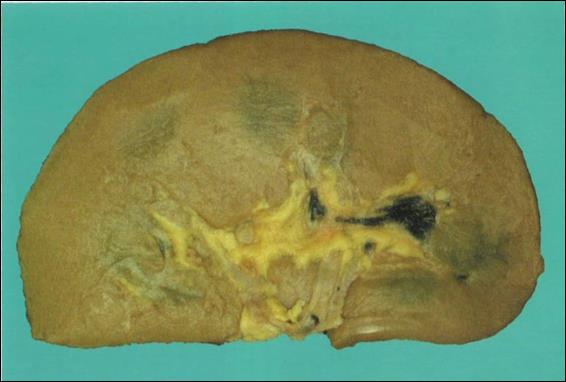

Рис. 22. Амилодоз селезенки, сальная селезенка.

В лимфоидных фолликулах, интиме артерий и красной пульпе по ходу ретикулярных волокон отложения розовых масс, вытесняющих ткань селезенки (1).